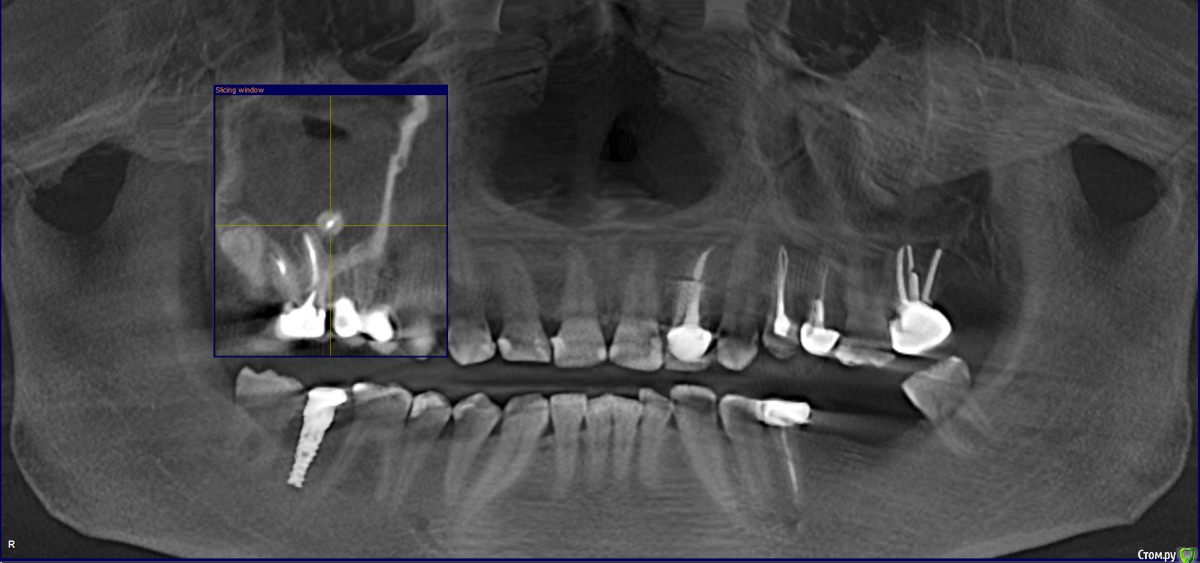

Jozjoz Опубликовано 8 марта, 2017 Поделиться Опубликовано 8 марта, 2017 Лет 8 назад удалял верхний зуб. Часть зуба попала в гайморову пазуху. КТ от октября 2016 года в приложении к теме. За эти 8 лет не было гайморитов и данный осколок никак меня не беспокоит. Вопрос:1. Обязательно ли удалять данный осколок зуба в ближайшее время (полгода) или можно потерпеть, пока не начнется гайморит (а он может никогда не начнется)?2. Я так понимаю операция называется гайморотомия. Предлагают сделать в амбулаторных условиях. Сколько дней после операции я не смогу работать в офисе ? 3. Может есть другие менее болезненные варианты удаления осколка зуба ? 4. Какие последствия возможны, если не удалять данный осколок зуба Спасибо большое Ссылка на комментарий

krokomot Опубликовано 8 марта, 2017 Поделиться Опубликовано 8 марта, 2017 По снимку у вас явная гипертрофия слизистой, то что должно быть запоненно воздухом, увас заполненно разросшейся слизистой практически вся пазуха, но тут еще нужно покрутить срезы кт. Может причина и не только в этом корне Ссылка на комментарий